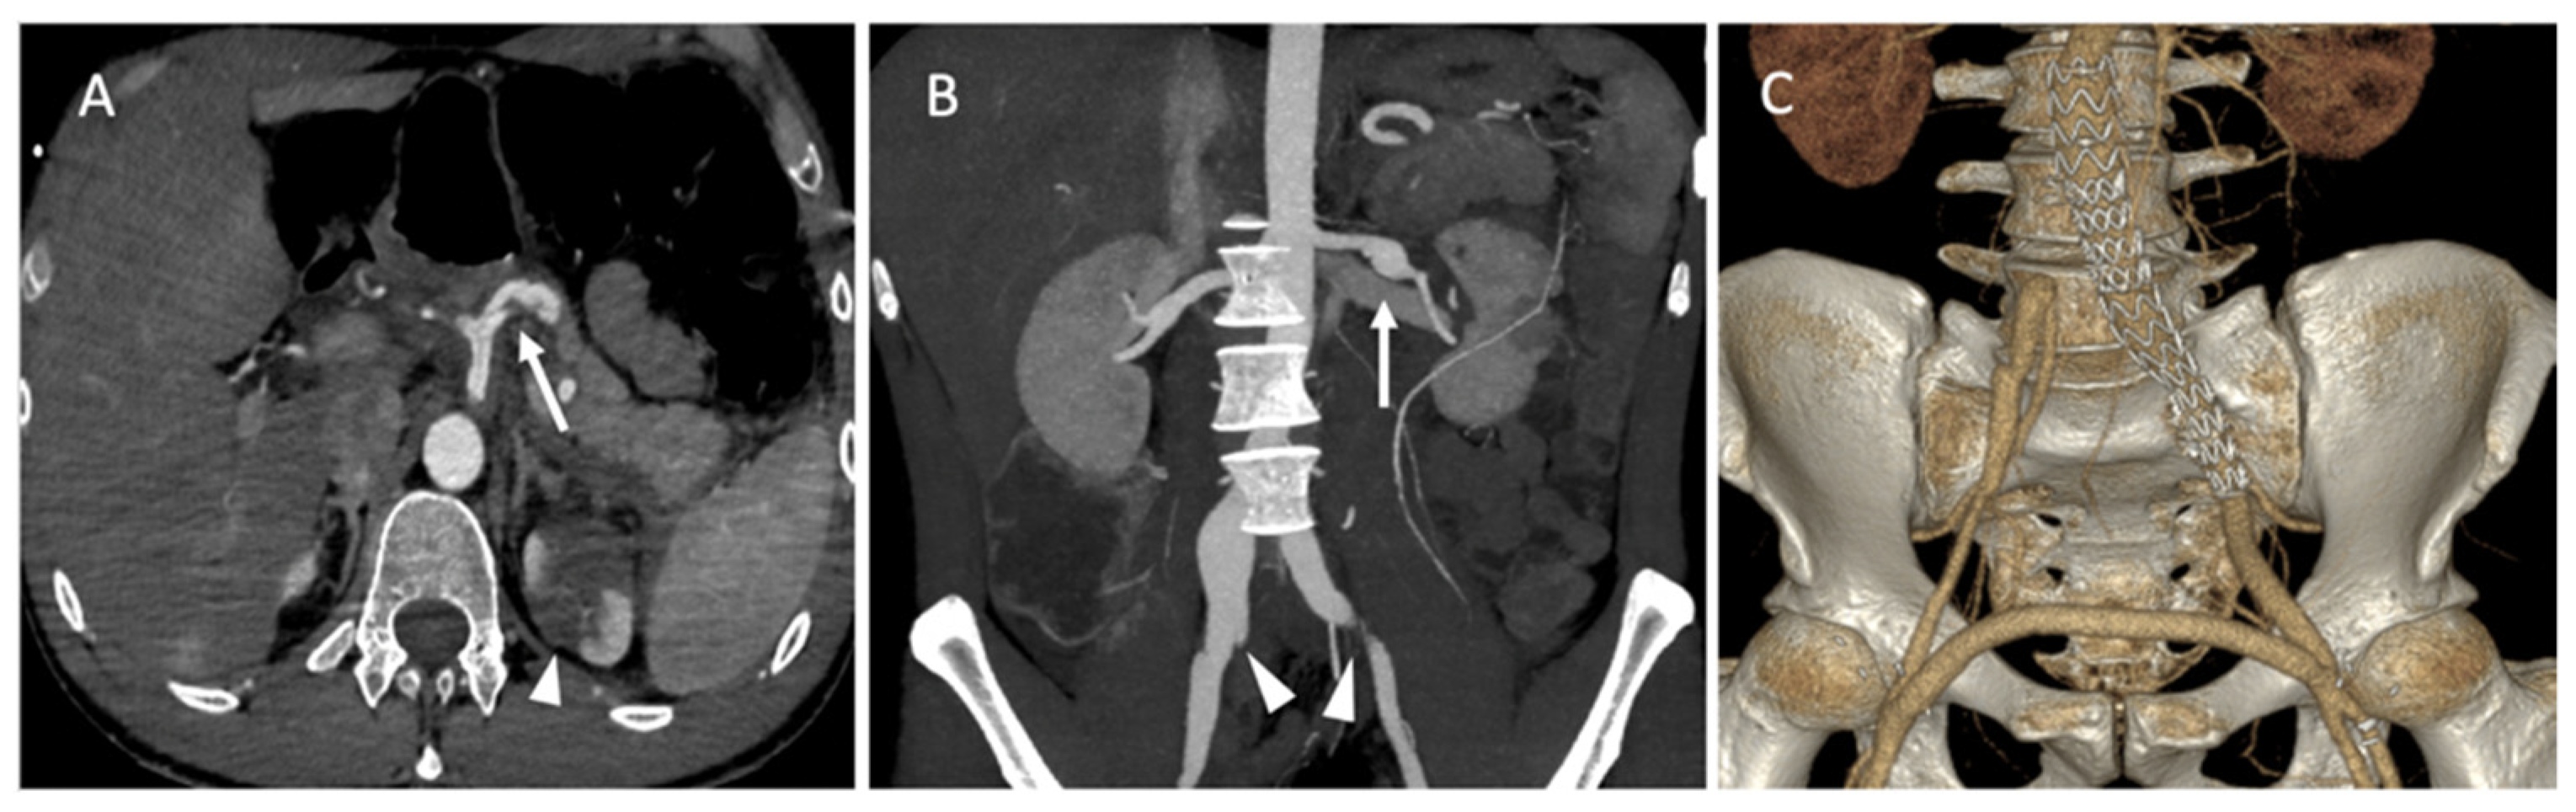

A 43-year-old female patient with a clinical and genetic diagnosis of vEDS (Gly mutation) visited our emergency room in a state of hemorrhagic shock. An enhanced abdominal CT scan showed a retroperitoneal hematoma surrounding the right kidney, with a ruptured aneurysm of the right renal artery. The patient was referred to the interventional radiologist. Under local anesthesia, the right renal artery was reached using a 6 F RDC catheter (Cordis-Santa Clara, CA, USA), and the right renal artery was then embolized using multiple IDCs and interlocking coils (Figure 7) without any complications during the procedure.

Figure 7.

(A) Digitally subtracted image from the right renal artery revealing the distal aneurysm with irregular walls (arrow). (B,C) Postembolization by coils.

2.5. Case 5

A 35-year-old male patient was admitted to the emergency department for acute abdominal pain. The CT scan showed a celiac trunk dissection extended to the hepatic and splenic arteries, a left renal artery dissection with an infarct and a right common iliac artery dissection with an aneurysmal formation (Figure 8A). The patient was monitored in the intensive care unit and treated with antihypertensive and analgesic anticoagulation therapy and strict rest. His clinical phenotype indicated vEDS according to the vascular medical team, and celiprolol was introduced. Four days later, he presented with recurrent abdominal pain associated with severe lumbar pain. A CT scan demonstrated a rapid diameter evolution of the left renal artery aneurysm and right common iliac artery dissection and a new dissection of the left common iliac and right renal arteries (Figure 8B). The pain regressed with blood pressure control and analgesics. A clinical and radiological follow-up was decided. One week later, due to the recurrence of lumbar and abdominal pain and aneurysmal evolution on two common iliac arteries, the patient was referred to a vascular surgeon and interventional radiologist. Under general anesthesia, we performed left hypogastric embolization by coils and endovascular exclusion of the left iliac artery with an aorto-iliac stent graft (Medtronic ETLW 16-10C124EE and ETEW 20-20C82EE). The contralateral iliac artery was embolized with second-generation 10 mm plugs (AMPLATZER-USA), and we performed a femoro-femoral bypass from the left to the right (Figure 8C).

Figure 8.

(A) Axial abdominal CT images in the arterial phase showing a celiac trunk dissection extended to the hepatic and splenic arteries (arrows) with renal ischemia; (B) coronal abdomen and pelvis CT images in the arterial phase showing common right and left iliac artery dissection (arrowheads); (C) the abdominal angiogram CT with 3D imaging reveals the left hypogastric embolization by coils and the endovascular exclusion of the left iliac artery with an aorto-iliac end prosthesis. The contralateral iliac artery was embolized with second-generation plugs and femoro-femoral bypass from left to right.

CT scan follow-up demonstrated an increase in the dissection of the left renal artery aneurysm, and multidisciplinary teams decided to refer the patient to interventional radiology for the embolization of the left retropyelic artery and prepyelic artery stenting. Under local anesthesia, a 6 F introducer was inserted into the left femoral artery, and the left renal artery was reached using a 5 F cobra catheter (COOK-MEDICAL). The left retropyelic artery was embolized with coils and a small amount of ethylene vinyl alcohol copolymer (Onyx, ev3, USA). Then, a two carotid wall stent (Boston Scientific, Marlborough, MA, USA) was deployed, 5 mm × 30 mm and 7 mm × 30 mm, in the prepyelic artery without any complications from the procedure (Figure 9).

Figure 9.

(A) Digitally subtracted image from the left renal artery dissection with aneurysm formation; (B) postembolization of the left retropyelic artery by multiple coils and a small amount of ethylene vinyl alcohol copolymer; (C,D) post-deployment of a two carotid wall stent in the left prepyelic artery.

The patient returned to intensive care for a few days. Then, he was monitored in the vascular surgery department, and the immediate postoperative period was uneventful. The patient was discharged at 30 days post operation. The patient was in good health after 10 months of follow-up by our vascular team, medication therapy with celiprolol and irbesartan, and physical activity adaptation. A regular to invasive progression has been observed thus far. The diagnosis of vEDS was confirmed by the identification of a pathogenic Gly variant in the COL3A gene.